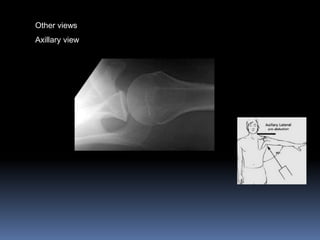

Other views of shoulder

Outlet or Neer`s view

Other views

Axillary view